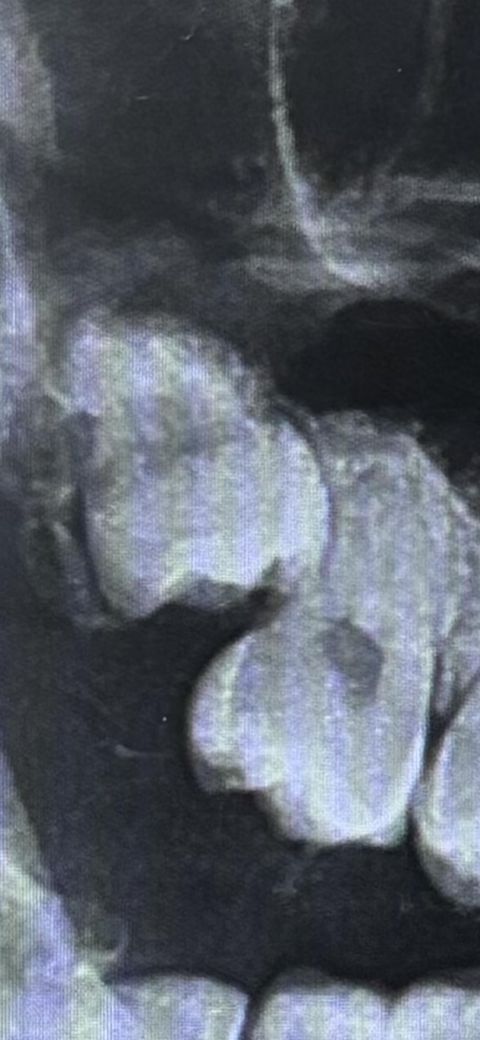

제가 아랫사랑니는 육안으로도 보여서 뽑아야 하구나 생각했는데 윗사랑니는 아직 안보이고 특히나 아프지도 않습니다. 병원에서는 안 뽑아도 될꺼 같다고는 하는데 사진 보시면 알겠지만 이상하게 나서 걱정이 되네요. 다른 병원가서 뽑을까요?

현재 사랑니가 앞의 어금에 닿아있어 방치시에 앞의 어금니를 상하게 하기에 빠른시일내에 발치를 하길 권합니다. 사랑니 발치 경험이 풍부한 구강외과 전문의가 있는 병원에서 발치를 권합니다.

사진상으로는 괜찮고, 별다른 증상이 없다면 현재로선 특별히 무리해서 빼줄 필요가 없는 상악 매복 사랑니로 판단됩니다.